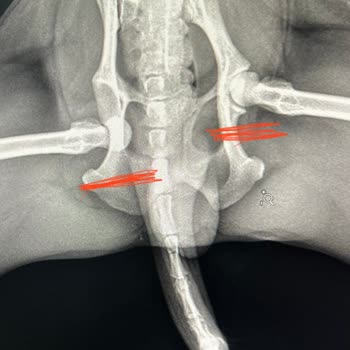

Müjde pet kuaförü köpeğimin sağ arka bacağını kalçasından çıkardı. Yarın ameliyat olacak. Tüm yasal haklarımı arayacağım! 3 yaşındaki köpeğimiz simba 6 Haziran günü sabah 11:00 de sapasağlam olarak girdiği Bostancı müjde pet kuaförden eve döndüğünde sağ arka ayağının üzerine basamadığını fark ettik...